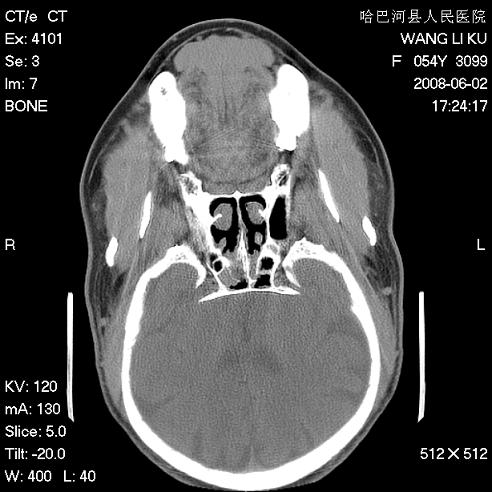

标题: CT13803:反复性鼻塞、流涕一年余 [打印本页]

标题: CT13803:反复性鼻塞、流涕一年余

1.全组副鼻窦炎2.双侧上颌窦积液

全组副鼻窦炎

1)全副鼻窦炎(左侧上颌窦黏膜下囊肿或息肉)。2)左眼眶肌锥内不规则小结节状软组织密度影;考虑为小血管瘤可能。建议行ct增强扫描检查。

全组副鼻窦炎,左侧肌锥内不规则形软组织肿块影,与眼外肌密度相当,左侧视神经受压,肿块与视神经及眼外肌分界清晰,眼外肌无增粗,眶壁无破坏,球后脂肪间隙不模糊,考虑良性改变,小血管瘤或神经源性肿瘤可能,建议增强扫描。

谢谢,增强扫描做了,眶内病灶与海绵窦同步明显强化,血管瘤